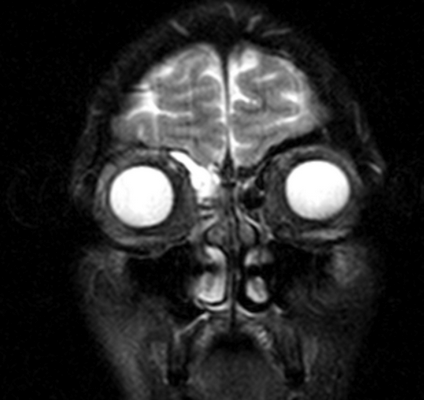

Магнитно-резонансное изображение измененной лобной пазухи

В основе МРТ лежит воздействие на организм магнитного поля, под влиянием которого меняется траектория движения протонов водорода. Томограф улавливает импульсы и преобразует их в картинку.

Водород есть в тканях, насыщенных жидкостью, поэтому МРТ детально показывает рыхлые структуры организма. Оборудование мощностью от 1,5 Тл дает подробные снимки изучаемой области. Изображения производят послойно, с шагом от 1-2 мм. Это позволяет выявлять патологические очаги размером от 3 мм.

МРТ пазух носа показывает мягкотканные элементы синусов. По характерным морфологическим изменениям, искажению сигнала, особенностям распределения контраста можно сделать выводы о наличии, распространенности и сути патологического процесса.